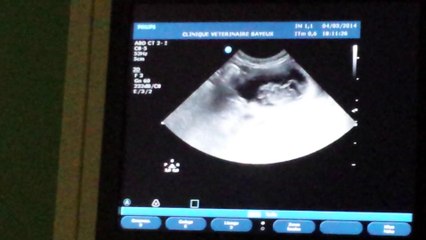

1ere echographie Daisy 20 jours de gestation

la grosse poche : c'est la vessie br quand on voit le doit : la vétérinaire nous montre le coeur battre